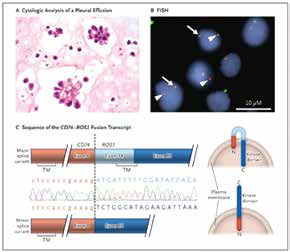

克唑替尼治疗ROS-1突变肺癌疗效获证

克唑替尼治疗ROS-1突变肺癌疗效获证

法国研究者Moro-Sibilot等报告,在ROS-1融合突变的晚期非小细胞肺癌(NSCLC)患者中,克唑替尼的活性得到验证;而在c-MET ≥ 6个拷贝数或c-MET突变的患者中,克唑替尼治疗2个…